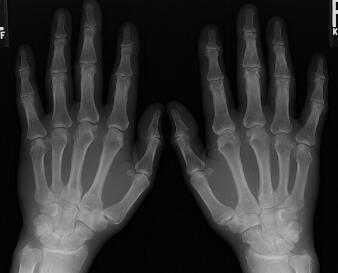

入院后,王怀庆主任马上为小吴安排了检查,症状:手关节肿胀、疼痛,早上有6分钟晨僵,膝关节肿胀,下蹲困难,行走时疼痛。X光检查结果:双膝关节未见脱位,关节间隙狭窄,关节面光滑,关节囊肿胀。化验:AS...[详细]

王怀庆主任为刘先生做了详细的检查。在经过认真查体后发现,刘先生双手指远端指间关节海伯登结节,关节僵硬,握拳无力。双膝肿胀Ⅲ°,皮温高,浮髌试验(+),屈100°伸-20°。...[详细]